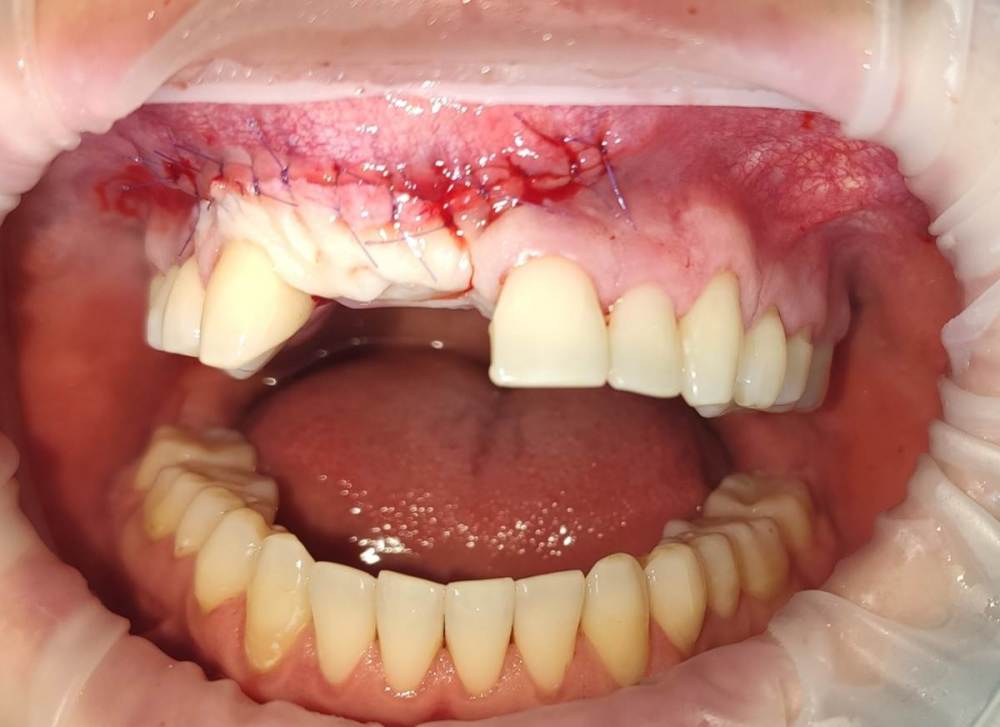

АнтонТЛТ Опубликовано 23 ноября, 2021 Поделиться Опубликовано 23 ноября, 2021 5 минут назад, Карен Аванесов сказал: Ничего что я к Вам спиной ахаха ахахахаахах))))))))))) Антон показывай все! Фото с операции нет. Но по разрезу можно догадаться что было сделано) жду созревания, чтобы имплантироваться. Ссылка на комментарий

Irouil Опубликовано 23 ноября, 2021 Поделиться Опубликовано 23 ноября, 2021 @АнтонТЛТ Я так понимаю по доступу, что тут Кюри? Ссылка на комментарий

АнтонТЛТ Опубликовано 23 ноября, 2021 Поделиться Опубликовано 23 ноября, 2021 5 минут назад, Irouil сказал: @АнтонТЛТ Я так понимаю по доступу, что тут Кюри? Нет швов в наиболее популярных донорских областях, Кюри я бы делал туннельно. Ссылка на комментарий

Irouil Опубликовано 23 ноября, 2021 Поделиться Опубликовано 23 ноября, 2021 10 минут назад, АнтонТЛТ сказал: Нет швов в наиболее популярных донорских областях, Кюри я бы делал туннельно. Не понял - как туннельно? Виста? Просто тут же тоже полулунный вестибулярный разрез? да, о донорской зоне не подумал. Цитопласт? Ссылка на комментарий

АнтонТЛТ Опубликовано 23 ноября, 2021 Поделиться Опубликовано 23 ноября, 2021 40 минут назад, Irouil сказал: Не понял - как туннельно? Виста? Просто тут же тоже полулунный вестибулярный разрез? да, о донорской зоне не подумал. Цитопласт? Да, виста. Для цитопласта или сетки я бы выбрал традиционный разрез по гребню. Но т.к. до меня в эту зону неоднократно лазили (видно по рубцам), то нарушение питания привело бы к расползанию раны в период ее заживления. Тут была "крыша гаража". 2 Ссылка на комментарий

АнтонТЛТ Опубликовано 25 ноября, 2021 Поделиться Опубликовано 25 ноября, 2021 6 часов назад, stommm сказал: Антон, как считаете, только десной можно было бы достичь приемлемого результата? Без удаления 11. Платформа или Масана например удачного заживления и продолжения На первой странице писал уже про работу с мягкими тканями. Были сомнения на счёт кровоснабжения, плюс подвижность 11 зуба присутствовала. В случае сильной резорбции кости, у меня есть запасной вариант. Можно будет сделать обратный ролл. Тут вестибулярно большой рубец. Можно его окклюзионно переместить. Нёбо уже ободрано до меня. 1 Ссылка на комментарий